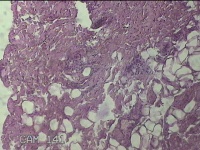

右侧耳垂结节

性别

男

年龄

24岁

临床诊断

耳垂新生物

一般病史

发现右侧耳垂结节3个月余。

标本名称

大体所见

灰白暗红色结节0.5x0.3x0.2cm一个,表面糜烂。

不具诊断价值。